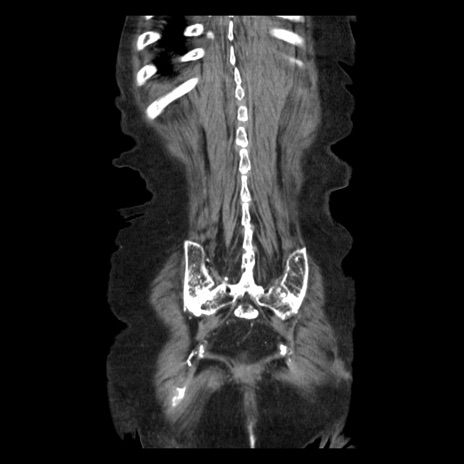

症例14(冠状断像)

【症例】 90歳代女性

【主訴】 腹痛・嘔吐

【現病歴】今朝から左側腹部痛を認めた。 経過観察していたが、嘔吐を認めたため来院。

【既往歴】 子宮癌術後

【身体所見】 意識清明、BP 127/54mmHg、P 98bpm Sp02 95%(RA)、BT 35.8°C、腹部平坦・軟腸ぜん動音聴取良好、右下腹部圧痛(+) 反跳痛なし

【データ】WBC 9800、CRP 0.46